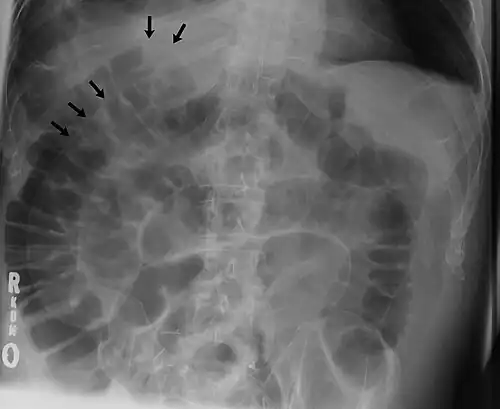

The double wall sign marks the presence of air on both sides of the intestine.[19] However, a false double wall sign can result from two loops of bowel being in contact with one another.[20] The sign is named after Leo George Rigler.[21] It is not the same as Rigler's triad.

Double wall sign. This is a secondary sign of pneumoperitoneum. Patient is supine, and air within the abdomen and lumen of the bowel accentuate both sides of the bowel wall. Double wall sign. This is a secondary sign of pneumoperitoneum. Patient is supine, and air within the abdomen and lumen of the bowel accentuate both sides of the bowel wall.